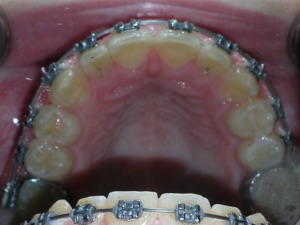

With a combination of braces, expansion and trimming we were able to bring it in. Watch!

Here are the results.